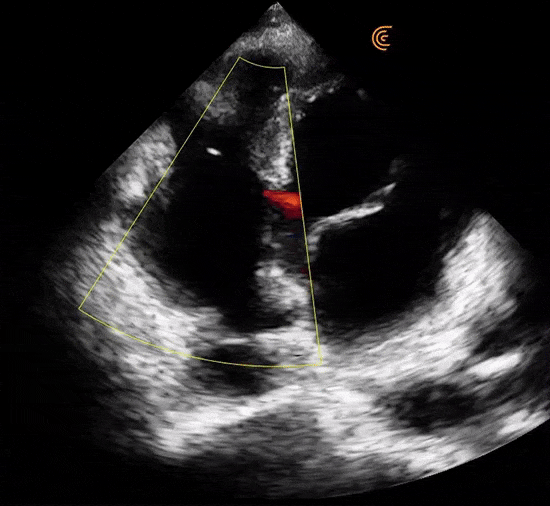

Visualize em cores e em tempo real a diferenciação entre as estruturas anatômicas. Tenha medidas automáticas e diversos recursos de otimização de imagem como o aprimoramento na visualização da agulha.

Com 192 elementos e tecnologia de 8 feixes, o Clarius entrega alta performance nos ultra portáteis com qualidade de imagem e recursos equiparáveis aos equipamentos high end convencionais.

Modos: B, B/M, Color, PDI, PW, Elastografia